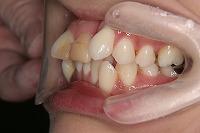

26歳4か月

右